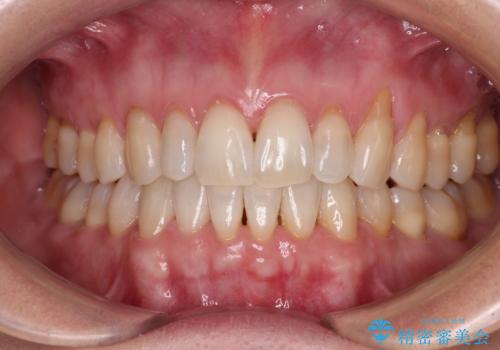

- 前歯の上下スペースによる食べにくさを気にして来院された患者様です。

インビザラインにより上下の前歯の隙間を閉じていくこととしました。

舌の突出癖があると上下前歯にスペースが開くため、矯正治療を機会に舌癖を改善するトレーニングを行ってもらい、矯正治療後の後戻りを防止するように指導しています。